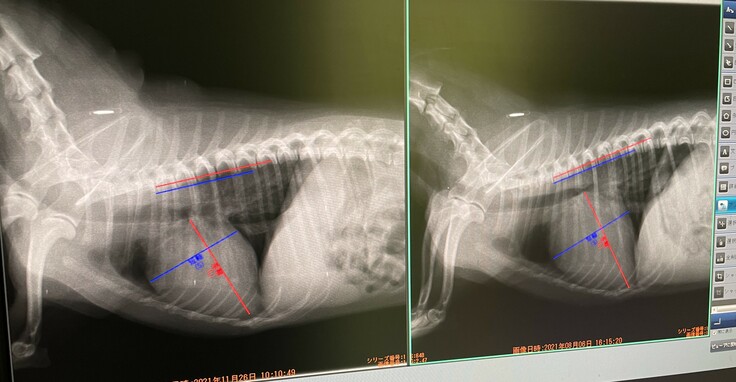

左が昨日、右が8月6日(手術前検査日)の画像です。

画像の拡大の数値が左右で違うようなので、心臓の大きさが左の

方が大きく見えますが、かなり小さくなり基準値以下のサイズとなりました。

また8月には気管が心臓に押しつぶされていたのが、画像でもはっきりと見えるほど改善し、咳は一切なくなりました。